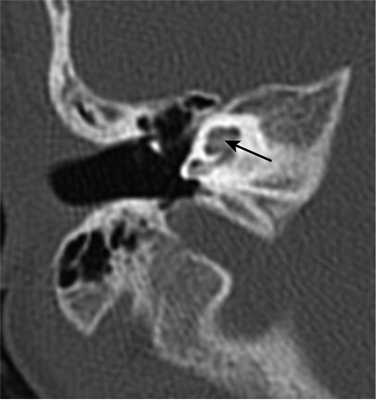

Один пациент, по данным КТ височных костей, имел двустороннюю облитерацию лабиринта, включая улитки с двух сторон, с большей выраженностью патологических изменений справа. На МРТ было выявлено уменьшение количества жидкости в улитке справа, слева количество жидкости в улитке соответствовало норме (рис. 1, 2).

Рис. 1. КТ, аксиальная проекция. Облитерация улитки (стрелка).